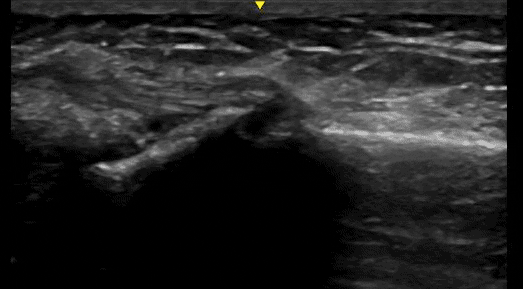

Case 2

Here we see a long axis view of a distal radius on a 79-year-old lady with a fall. In this case, there is a non-displaced fracture, which is actually more clear on the ultrasound than the X-ray. This fracture is clearly not angulated.